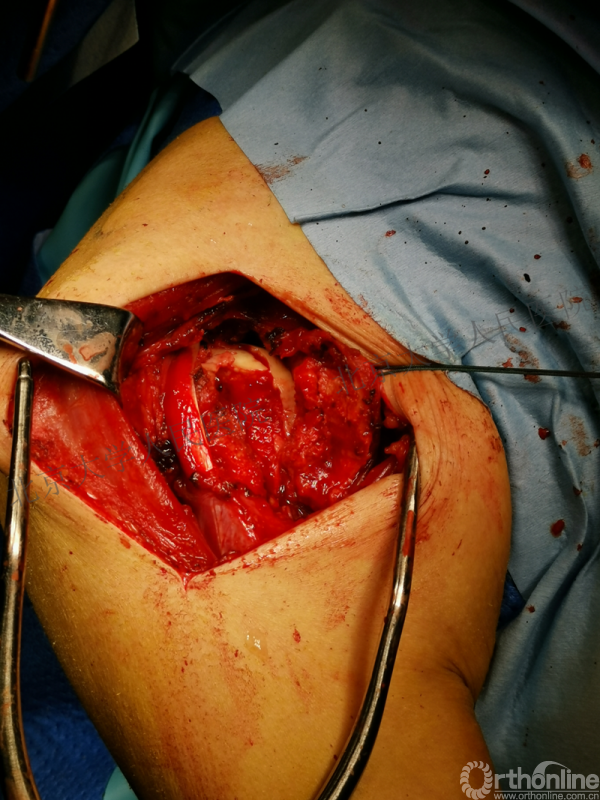

全麻下行切开复位内固定术,备植骨+关节镜检

胸大肌三角肌间隙入路

操作步骤